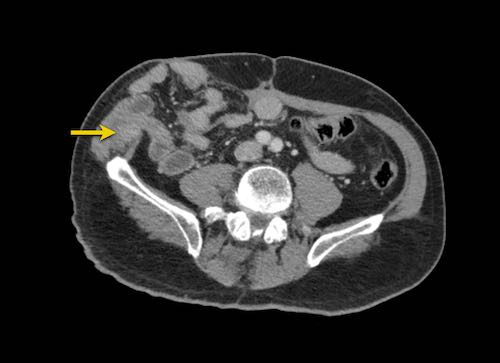

Hình ảnh

Hình ảnh CT của một bệnh nhân ung thư phúc mạc.

Một lượng nhỏ dịch cổ trướng hiện diện ở góc phần tư trước bên phải.

Các đường dày dạng nốt vuông góc với thành ruột được ghi nhận.

Hình ảnh này đại diện cho tổn thương xâm lấn mạc treo ruột lan rộng (mũi tên).